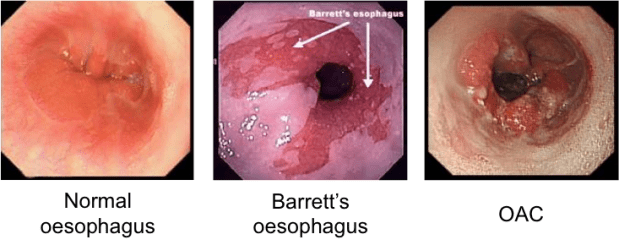

As we know cancer occurs as a result of uncontrolled proliferation (growth) of abnormal cells, in this case in the oesophagus. Oesophageal cancer commonly takes one of two forms namely Squamous Cell Carcinoma (SCC) or Oesophageal Adenocarcinoma (OAC), with recent years seeing a rise of the latter. One common risk factor for OAC is thought to be a condition known as Barrett’s Oesophagus, which develops in response to prolonged exposure to stomach acid and bile due to gastro-oesophageal reflux disease (GORD). This exposure can trigger changes in the types of cells found in the lining of the oesophagus. However, whether Barrett’s Oesophagus is always required for disease progression has yet to be confirmed. Also missing from our understanding is any real clear molecular insight into the changes occurring between normal oesophageal cells and resulting carcinomas. Thus it is no wonder that OAC is associated with a poor prognosis and five year survival rate of just 14%.